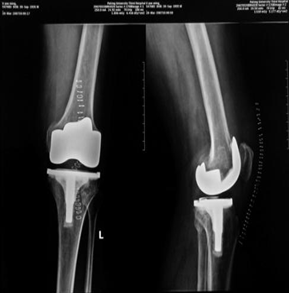

人工全膝关节置换术

人工全膝关节置换术是在近代人工全髋关节成功应用于病人后,逐渐发展起来的一种治疗膝关节疾病的新技术,它能非常有效的根除晚期膝关节的疼痛,极大地提高病人的生活质量,在发达国家比较流行,根据美国HSS评分标准,手术优良率高达93.75%,术后在疼痛、关节功能及活动度等方面均有明显改善。

我院已经开展了此项技术的应用,并在近几年内成功完成多例手术,术后均取得了良好的效果,随访的患者均得到了满意的疗效。由此结论,人工全膝关节置换术是现今治疗重度膝关节疾病的切实有效的方法。